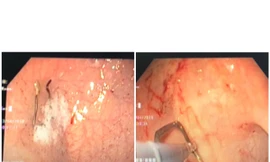

TPO - Người phụ nữ được đưa đến bệnh viện trong tình trạng chướng bụng và đau dữ dội mà không rõ nguyên nhân. Các bác sĩ tiến hành nội soi thì phát hiện trong tá tràng của người phụ nữ có dị vật là que tăm xỉa răng, một đầu đã đâm xuyên thành tá tràng.